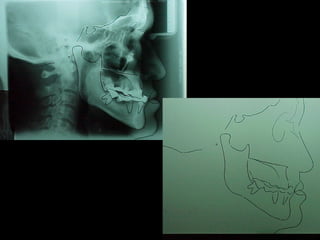

Cefalometría elementalCefalometría elemental

Deflección craneal 26º

Longitud craneal anterior 59 mm.

Altura posterior facial 59 mm.

Posición de rama mandibular 78º

Localización de Porión 38 mm.

Arco mandibular 30º

Longitud de cuerpo mandibular 81 mm.

Se observa el número total de órganos dentarios incluyendo

terceros molares.

No hay tratamiento de conductos radiculares

Buen trabeculado óseo de tipo I